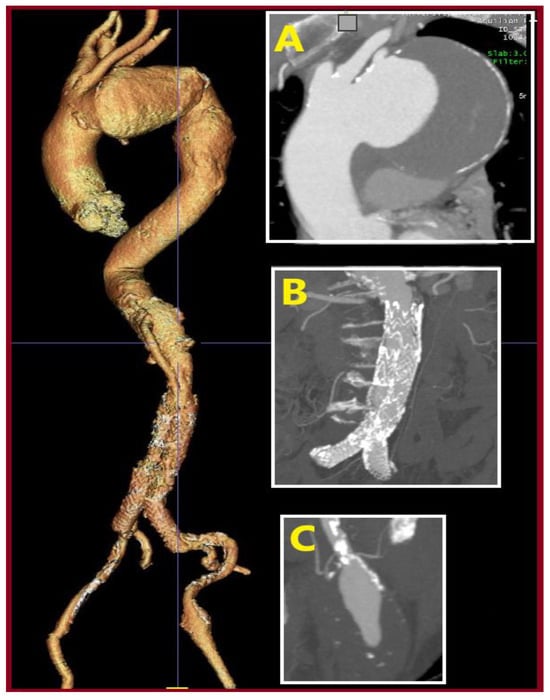

Show Figures

Figure 1